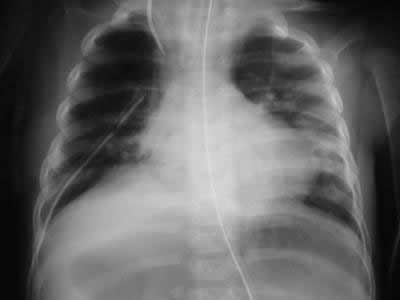

Radiología del tórax

• Rx torax PA: Observamos elevacion del diafragma derecho, y leve dezplazamiento izquierdo del mediastino anterior, atelectasia laminar basal derecha.

Rx torax: eventracion diafragma